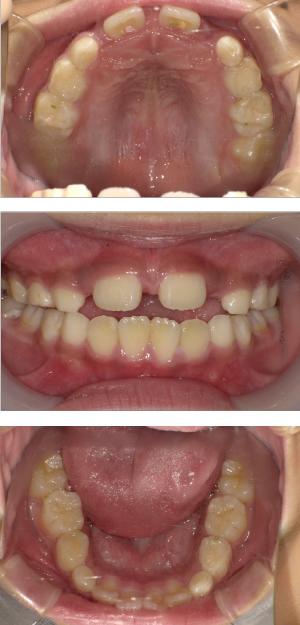

バイオブロック矯正(顎顔面口腔育成治療)

矯正治療は大人になって始めるよりも子どもの頃から始めた方が確実に良い結果をもたらします。成長が盛んな子供の時期に、顎や顔の成長を利用しながら治療ができる大きなメリットがあるからです。当院では、非抜歯矯正を推奨しておりバイオブロック矯正を取り入れています。

バイオブロック矯正の考え方は歯並びが悪くなる原因にアプローチする治療法になります。

舌の位置や口呼吸から乱れてしまった下顎の後退を正し、顎顔面が本来あるべき位置へと誘導させていく治療です。

- 歯並びの改善